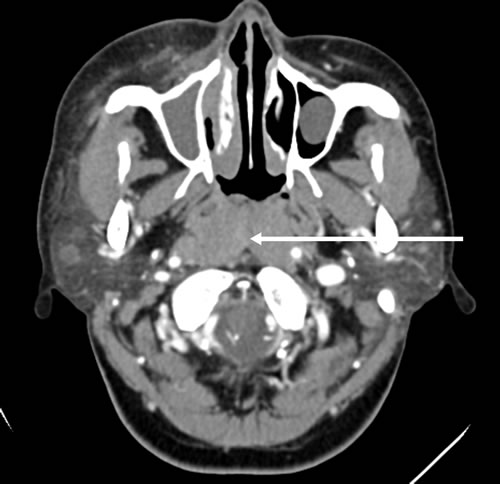

A 21-year-old male was hospitalized with a ten-month history of nasal blockage and a fever of one month duration. He presented with nasal blockage in the right side at the time of initial presentation, without nasal discharge, headache or tinnitus. Despite symptomatic treatment, he continued to do poorly and had persistent nasal blockage. He developed persistent fever a month ago, beginning at nightfall and peaking to 39 °C to 40 °C during the night or in the early morning. Meanwhile, a soy-like, painless and gradually increasing mass in the right submandibular area was found which was not responsive to antibiotic treatment. Fever improved when he received dexamethasone, and his temperature increased again when dexamethasone was withdrawn. Contrast computed tomography (CT) showed that the nasopharyngeal mucosa was thickened (Figure 1) and the celiac and retroperitoneal lymphaden was intumescent (Figure 2). Bone marrow aspiration and CT scan of chest and neck show normal. Finally, the biopsy based on nasal endoscopy and examination by flow cytometric methods confirmed a diagnosis of nasal NKTCL (Figure 3, Figure 4). According to the Ann Arbor staging, this patient was IIIB of the disease.

Figure 1: Contrast brain computed tomography shows diffuse swelling of the posterior wall of the pharynx with mild enhancement.

Our patient first presented with nasal blockage, and the following computed tomography showed that the nasopharyngeal mucosa was thickened. Localized inflammation and tumor are the most likely diagnosis for this person. Nasopharyngitis and nasopharyngeal carcinoma (NPC) could cause thickening of nasopharyngeal mucosa, both of which are associated with viruses. NPC has a high incidence in southern China and Hong Kong, with an incidence of 25 to 50 per 100,000 people [3]. Osteoma, papilloma, and carcinoma are relatively rare but are important potential causes and are responsible for tumors which may cause nasal blockage [4].The main symptoms are unilateral, slowly increasing blockage of the nose with or without bloody-purulent secretion and impairment of olfaction. In later stages of the disease, epistaxis and facial swelling can occur [5-6] and further progression can lead to ulceration and painful mid-facial destruction. The lymphoma could spread to the skin, gastrointestinal tract, testis, spleen and central nervous system [7]. However, nasal NKTCL could also lead to destruction and loss of function of the upper respiratory tract, especially in the nasal cavity, nasal and paranasal sinuses, and hard palate [8], which has been associated with Epstein barr virus infections [9].